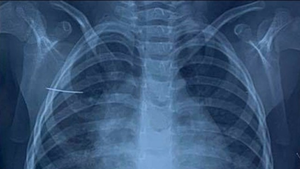

Theo gia đình bệnh nhi, trong lúc chơi đùa bé gái ở huyện Bình Giang, tỉnh Hải Dương đã vô tình nằm đè vào chiếc kim khâu.